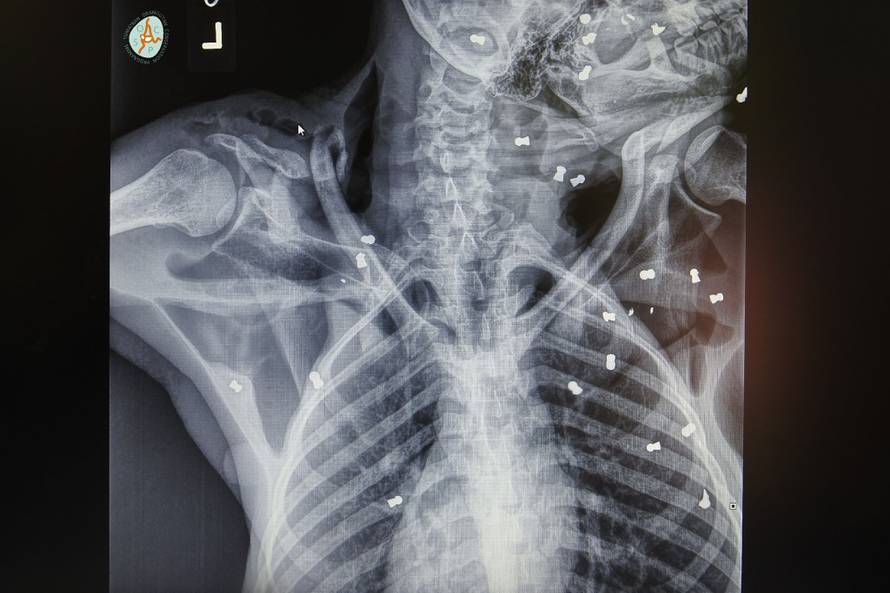

Stravična sudbina orangutana: Upucali ga iz zračnice 74 puta

Sudbina orangutana Hope je najstrašnija od svih ozlijeđenih životinja na koje smo ikad naišli. Nezamislivo je da ovakvo nešto može napraviti čovjek, kažu u Organizaciji za očuvanje orangutana na Sumatri